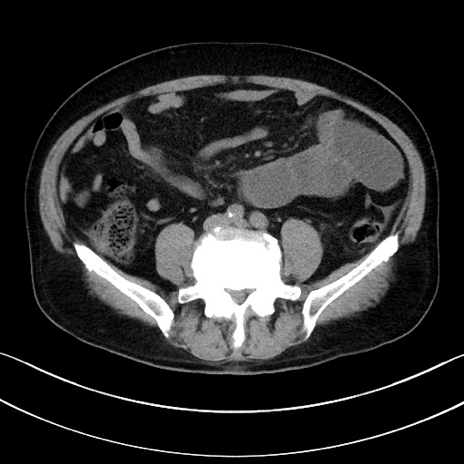

症例

冠状断像